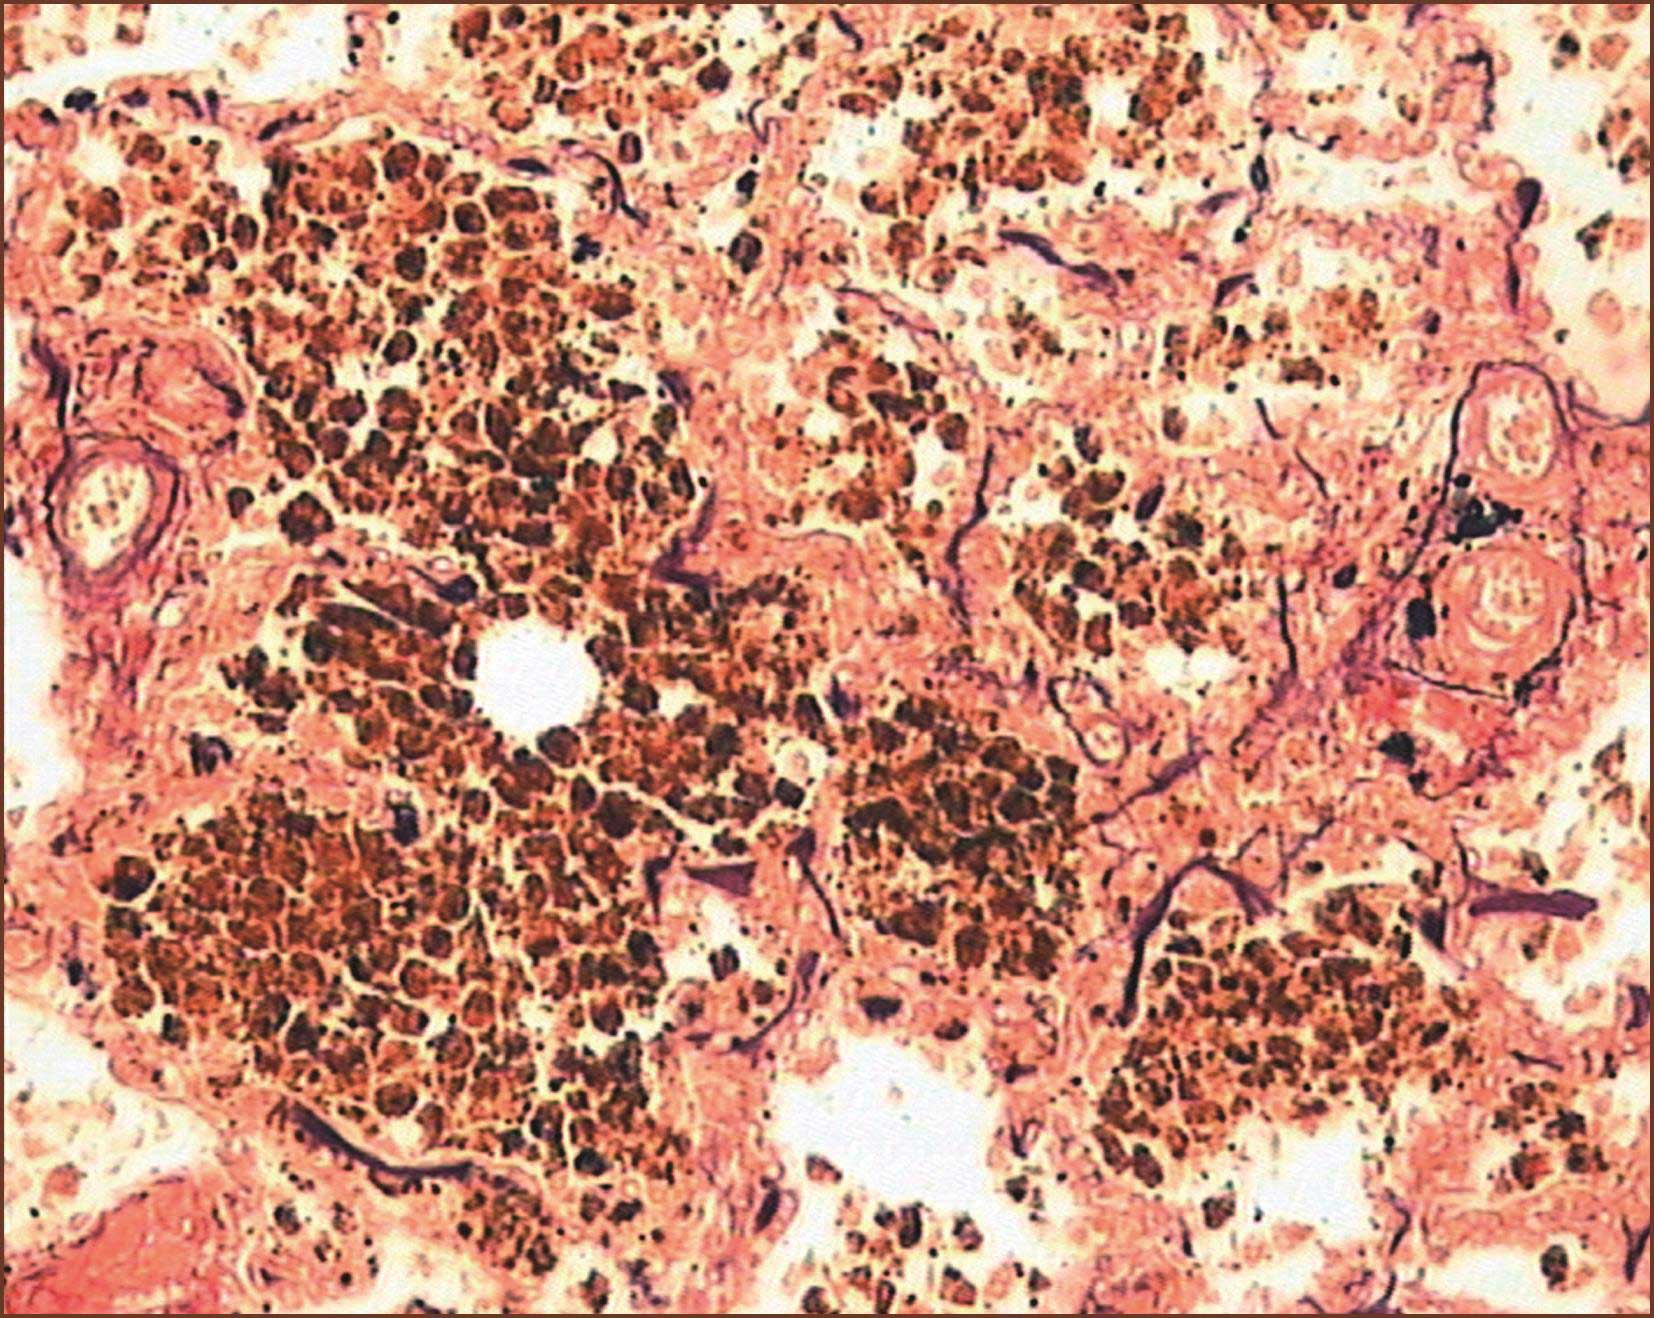

(八)肺毛细血管瘤样增生症

肺毛细血管瘤样增生(pulmonary capillary haemangiomatosis,PCH)是另一罕见的肺动脉高压,特征是在肺组织内有局限性毛细血管、小静脉增生,增生的微血管侵入肺间质、血管或气道周围成团块状,低倍镜下类似肺充血,仔细观察为弥漫性微血管增生,内含大量红血细胞。此增生的微血管可形成球状或结节状,增生的内皮细胞中少见核分裂象。异常增生的微血管可侵至肺细小动脉、细小静脉壁并阻塞管腔,也可侵入附近的神经、胸膜和淋巴结。

在肺微血管病,可见肺小动脉明显的肌性肥厚及内膜纤维化增厚。但不像PVOD,血栓形成不是其特征。静脉闭塞在PVOD是由于内膜纤维化;而在肺微血管病则是由于微血管增生。在肺微血管病未见丛状病变。

关于本病的发生学说,争论不一。肺微血管病在临床表现类似IPAH,主要靠组织病理学来鉴别和确诊。我们遇到的肺微血管(细小静脉和/或毛细血管)瘤样增生是在丛源性肺动脉病、COPD-PH和风湿性二尖瓣病的尸检肺组织内。